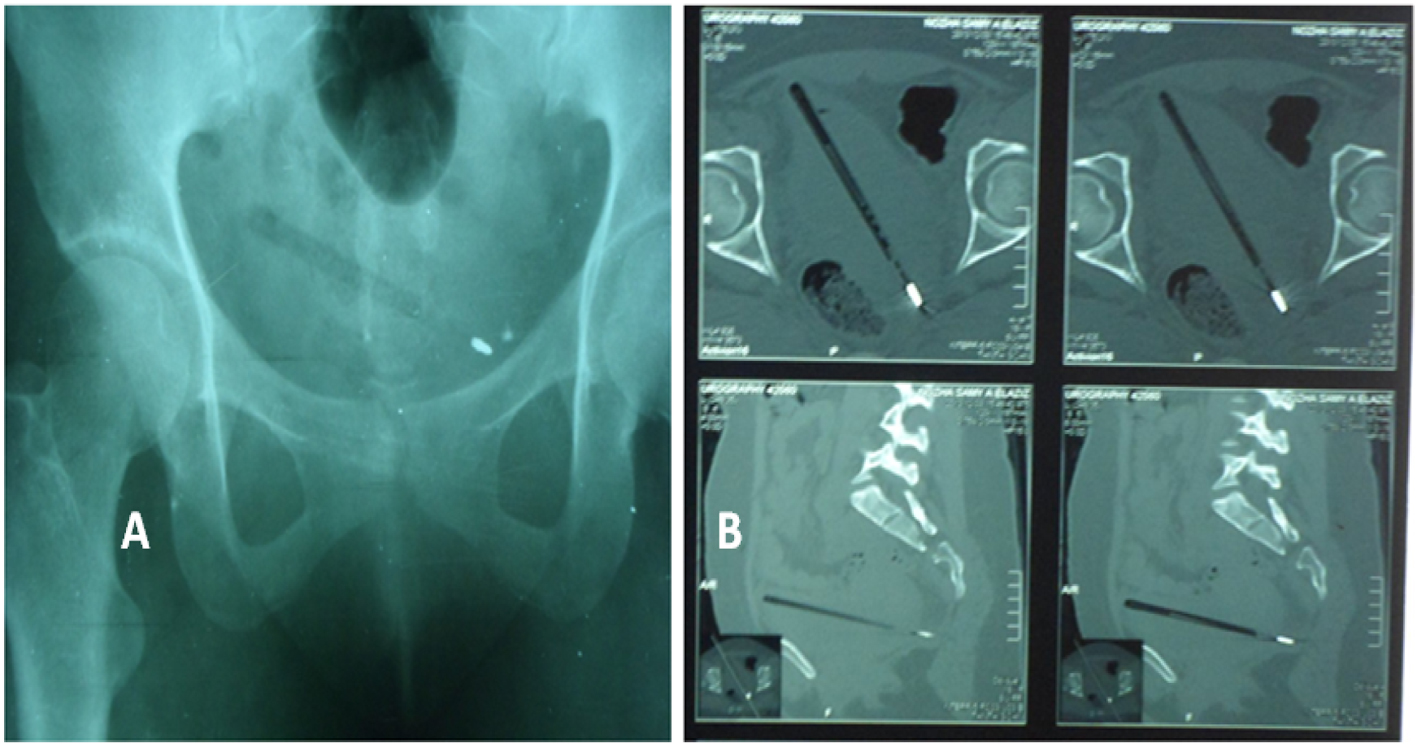

An 18-year-old female patient presented to our emergency department complaining of severe dysuria, hematuria and suprapubic pain which occurred after self-insertion of a pen inside the bladder during masturbation. Physical examination revealed suprapubic tenderness on palpation. Genital examination was normal and hymen was not ruptured. Laboratory findings were normal except urine analysis showed RBCs over 100. Ultrasound, X-ray pelvis and computed tomography confirmed the presence of a pen inside the bladder (Fig. 1A, B). Under general anesthesia, visualizing cystoscopy was performed and the pen was successfully extracted (Fig. 2, 3). The operative time was 35 min with no intraoperative complications. Twenty °F Foley’s catheter was inserted for 10 days to ensure complete healing of the minor bladder perforations. Her postoperative recovery was satisfactory.

![]() Click for large image | Figure 1. (A) Plain-X-ray showing the pen (radio-opaque shadow is the metal tip of the pen). (B) Computer tomography showing the pen is hanged inside the bladder. |